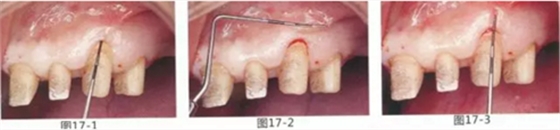

為了在左上1,2,3,4部位增加附著齦,左上1,2部位用Apically Positioned Flap(齦瓣根尖側(cè)轉(zhuǎn)移),左上3,4部位用游離齦移植的病例

圖17-1~3 左上3的牙周袋探測(cè)值為3mm,角化牙齦寬度為2mm。也就是完全不存在附著齦,如果這種狀態(tài)下佩戴修復(fù)體的話,很有可能發(fā)生頸部暴露等問題。

圖17-4 左上1,2進(jìn)行齦瓣根尖側(cè)轉(zhuǎn)移,左上3,4進(jìn)行游離牙齦移植,在去除牙周袋的同時(shí)獲取附著齦。

圖17-5 牙周治療完成后的正面照。左上3,4部位處游離齦移植片的上端通過骨膜縫合固定在頰側(cè)嵴頂部。這樣可以使其愈合效果與齦瓣根尖側(cè)轉(zhuǎn)移相同。